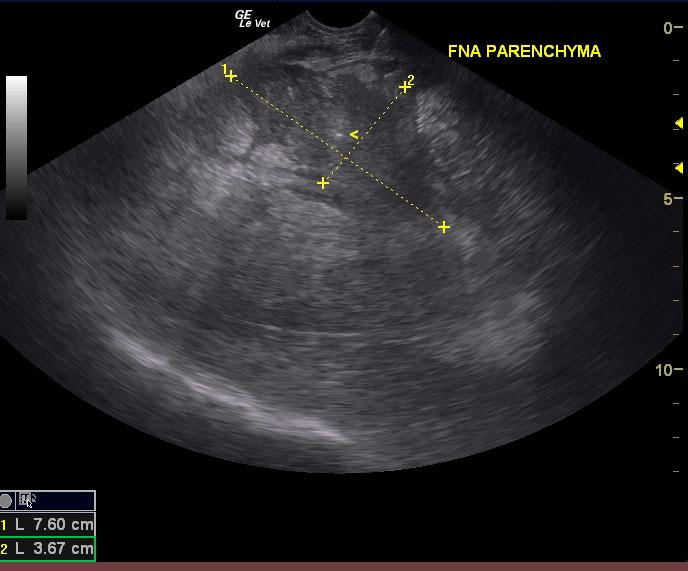

A 7-year-old MN Labrador Retriever was presented for severe hind limb swelling, bruising in the inguinal region (Image 1) and grade 3 limp. Mild fever was present. Radiographs revealed severe soft tissue swelling of around the femur without bone involvement. Thoracic and abdominal radiographs were unremarkable.

A 7-year-old MN Labrador Retriever was presented for severe hind limb swelling, bruising in the inguinal region (Image 1) and grade 3 limp. Mild fever was present. Radiographs revealed severe soft tissue swelling of around the femur without bone involvement. Thoracic and abdominal radiographs were unremarkable.